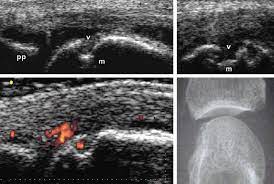

Ecografie Pluridistretto con Power Doppler per Pazienti Reumatologici a

Palermo

Questo servizio è particolarmente innovativo. Le Ecografie Pluridistretto con Power Doppler a Palermo permettono di valutare più articolazioni nella stessa seduta, con un’analisi approfondita dell’attività infiammatoria.

Il Power Doppler consente di:

-

Valutare la vascolarizzazione

Identificare infiammazioni attive

Monitorare l’evoluzione di patologie reumatologiche